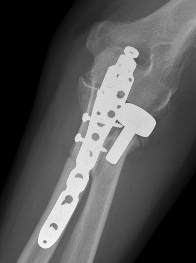

ORIF olecranon with plate +/- LCL repair

- posterior approach and plate olecranon

Olecranon plate + ORIF Type II coronoid process + radial head replacement

Olecranon plate with radial head replacement

Olecranon plate with radial head replacement + LCL repair

Olecranon plate + medial coronoid buttress plate + radial head replacement